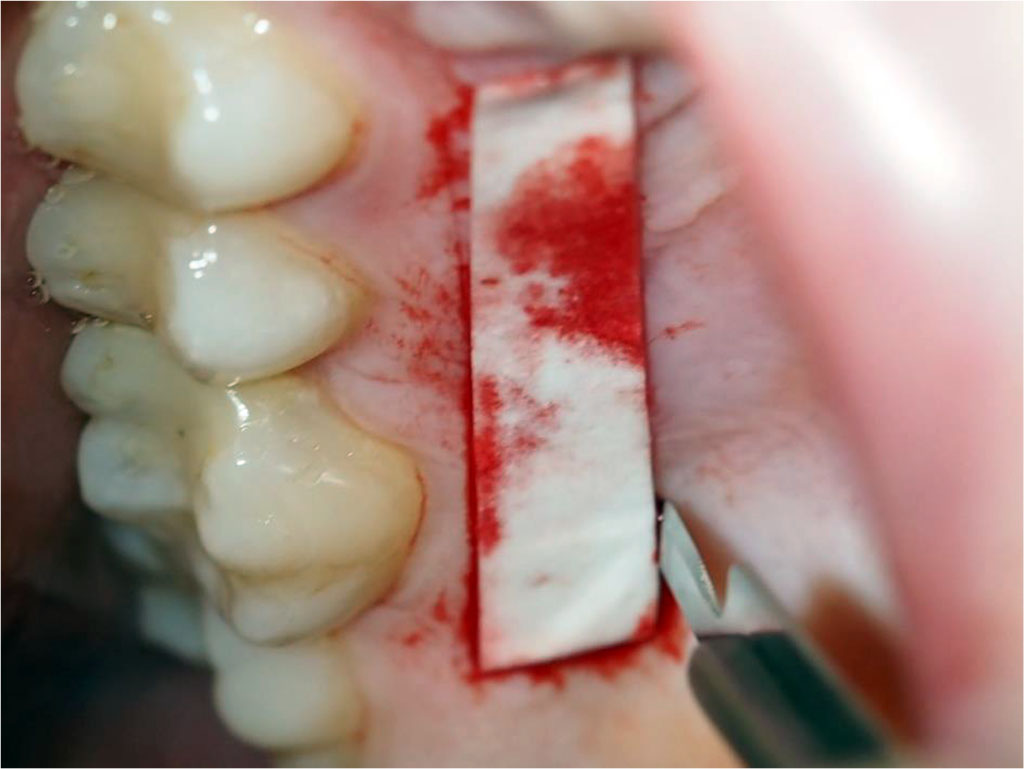

The patient was qualified for peri-implant soft tissue augmentation using the tunnel technique and a subepithelial connective tissue graft (sCTG) taken from the palate. The procedure was discussed, post-operative recommendations were explained and written informed consent was obtained for the procedure. One Shot - 2g of Amoxycyllin was administered 1h before surgery - perioperative antibiotic prophylaxis. Prior to the procedure, the patient had blood drawn from the ulnar vein to obtain Advanced Platelet Rich Fibrin (A-PRF) membranes to secure the donor site located on the palate (Fig.2). Infiltration anaesthesia of the donor site and conduction block anaesthesia of the greater palatal orifice with articaine 1:100000 was administered. With use of preoperatively prepared template (Fig.3), an epithelial-connective tissue graft was harvested from the palate using the free gingival graft (FGG) technique (Fig.4). A larger amount of sCTG was harvested due to the need to simultaneously cover gingival recessions in the left maxillary region. The graft was then de-epithelialised (Fig.5). The donor site wound was secured with an A-PRF membrane and crossed 5-0 non-resorbable mattress sutures (Fig.6). Under infiltration anaesthesia of the recipient site with a 1:100,000 preparation of articaine in area 12-14, a supraperiosteal tunnel was dissected (Fig.7). An sCTG was then inserted into the tunnel (Fig.8) and 6-0 non-resorbable sutures were placed to position and stabilise the graft in the intracoronal position (Fig.9). Oral rinsing with 0.1% chlorhexidine digluconate for 2 weeks, and postoperative instructions were prescribed. Wound toileting was performed at the follow-up visits each time.

Fig.3 The template size was determined based on the recipient site to accurately harvest the required amount of tissue from the donor site.